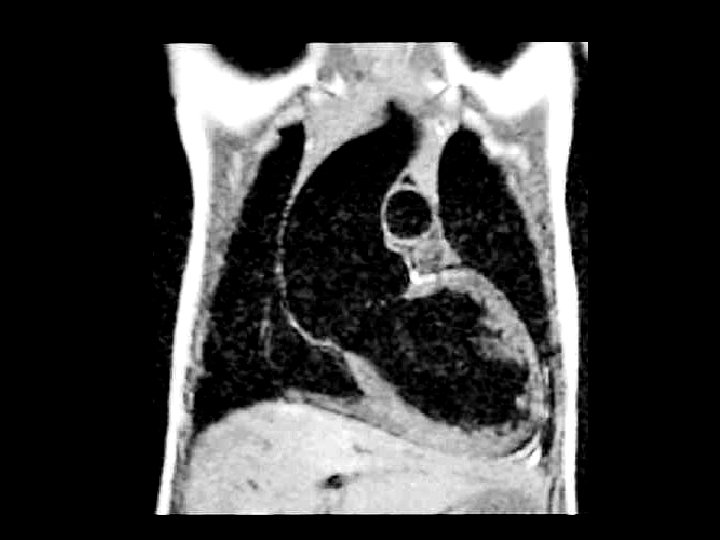

Rhabdomyoma • Findings: – right atrial mass with partial obstruction of the inferior vena cava • ddx: – myxoma – lipoma – angiosarcoma